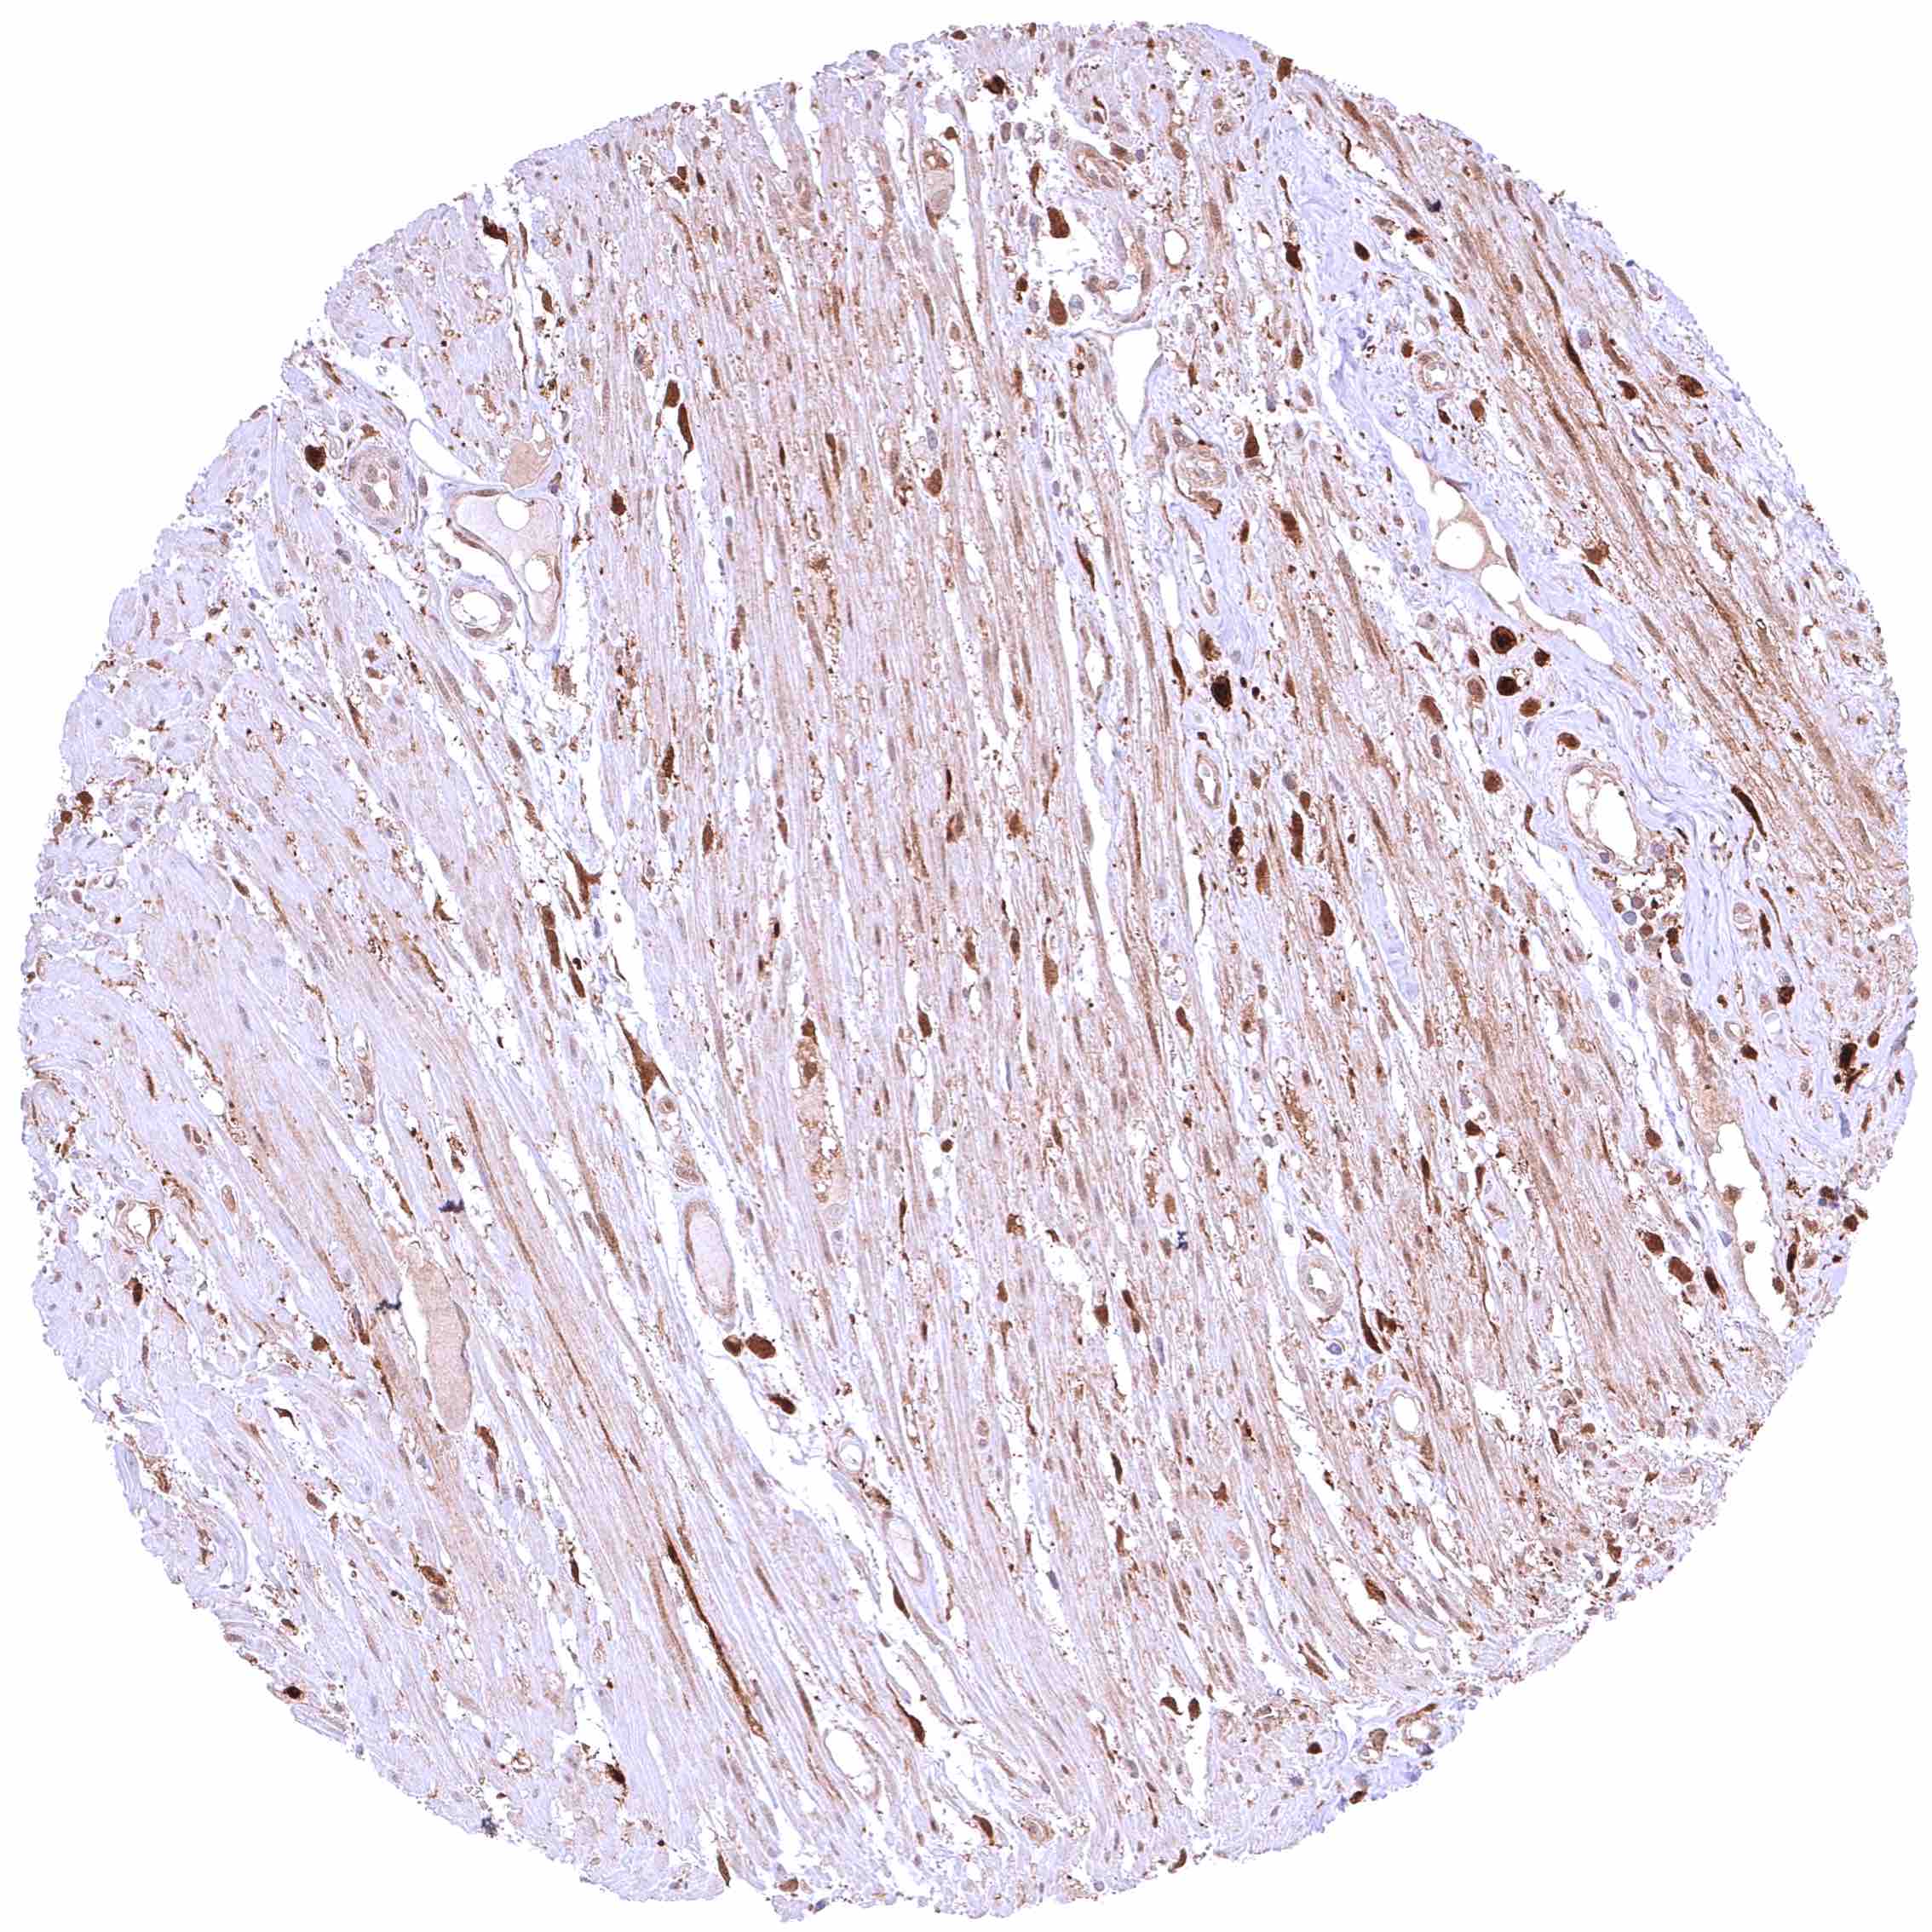

Uterus, myometrium – Distinct, nuclear and cytoplasmic GSTP1 positivity of muscle cells.